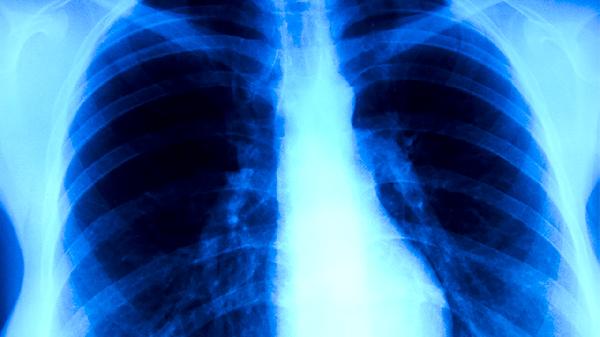

X光胸透可以检查出部分肺癌,但存在漏诊概率。肺癌筛查主要依赖低剂量螺旋CT,X光胸透对早期肺癌的检出率较低,可能遗漏小结节或特殊位置的病灶。

X光胸透作为一种基础影像学检查,能够显示肺部较大肿块、肺门增大、胸腔积液等中晚期肺癌的典型表现。对于直径超过2厘米的中央型肺癌,尤其是伴有阻塞性肺炎或肺不张的情况,胸透检查通常能发现异常阴影。胸透的优势在于操作简便、辐射剂量低且成本较低,适合大规模体检筛查。

胸透对早期周围型肺癌的检出率不足30%,可能漏诊小于1厘米的肺结节、磨玻璃样病变以及被心脏或横膈遮挡的病灶。部分肺泡癌或沿支气管壁生长的肿瘤在胸透中仅表现为局部纹理增粗,容易与肺炎或结核混淆。对于高危人群如长期吸烟者,胸透阴性结果不能完全排除肺癌可能。

建议40岁以上吸烟人群每年进行低剂量螺旋CT筛查,该技术能发现90%以上的早期肺癌。若胸透发现可疑阴影,需进一步通过增强CT、PET-CT或支气管镜检查明确诊断。同时应结合肿瘤标志物检测和临床表现综合判断,避免单一依赖胸透结果延误治疗时机。